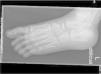

En las radiografías solicitadas (figs. 1–3) no se evidencian líneas de fractura, objetivándose un escafoides aumentado de densidad, con morfología en disco, esclerosis y fragmentación siguiendo un eje lineal. Estos hallazgos son sugerentes de necrosis aséptica del escafoides o enfermedad de Köhler.

Radiografía oblicua del pie izquierdo en la que se aprecian los mismos hallazgos descritos en la figura 1.

Detalle de la figura 1 en la que se aprecia el hueso escafoides aumentado de densidad con morfología en disco, esclerosis y fragmentación siguiendo un eje lineal. Hallazgos indicativos de necrosis aséptica.